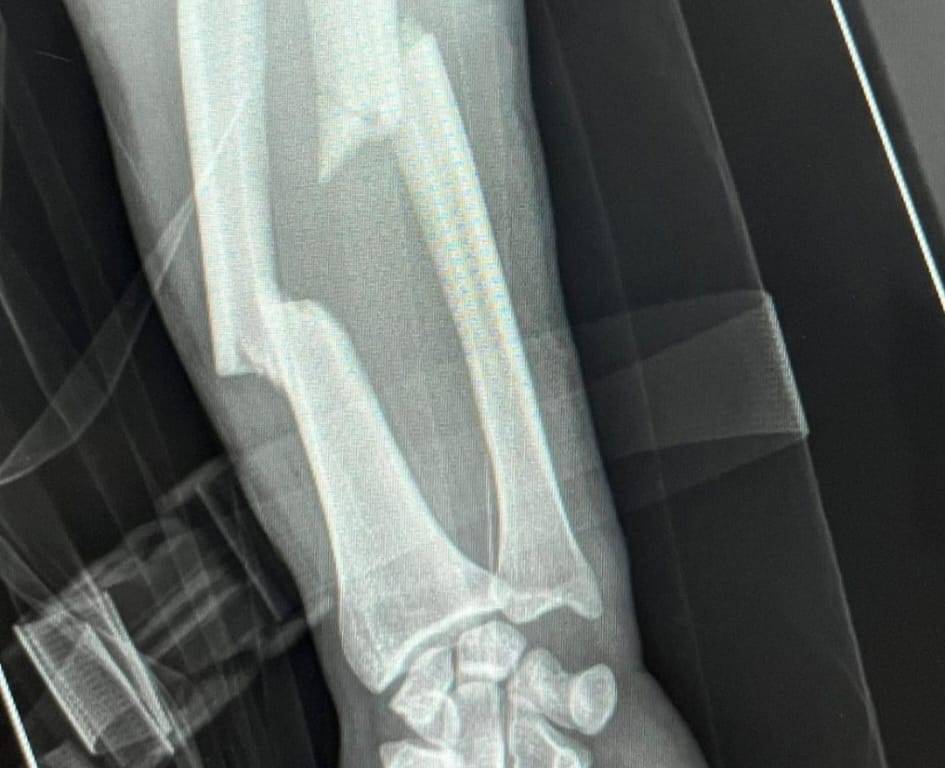

Asi se puede ver lo que ha significado el desafortunado percance de este sabado en la localidad gala de Saint Vincent de Tyrosse. Ya queda, tras operársele ese mismo día en la noche en Dax, una recuperación contra reloj, para de esta manera estar volviendo a los ruedos cuando los tiempos de rehabilitación asi lo indiquen. No es fácil la empresa, pero no imposible para el joven y atlético coleta taribense, quien asume su percance más cuesta arriba, pues siempre las lesiones óseas son las más complicadas y tardías de recuperarse que las mismas cornadas, donde el tejido muscular es más rápida su evolución que las fracturas. Y en Jesús Enrique está la recuperación de dos huesos como son el cubito y radio del antebrazo izquierdo.

Atentos a la evolución que vaya mostrando Jesús Enrique “Colombo” tras su desafortunado percance el pasado sabado en Saint Vincent de Tyrosse. La radiografía muestra el alcance del desafortunado derrite del toro cuando entraba matar. Foto: Cortesía